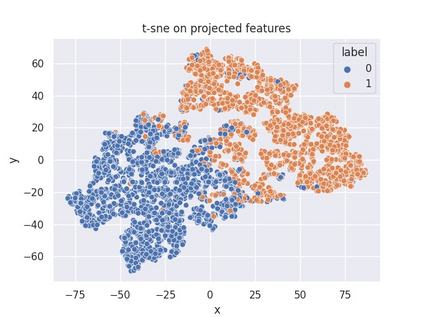

Multiple instance learning (MIL) is a powerful approach to classify whole slide images (WSIs) for diagnostic pathology. A fundamental challenge of MIL on WSI classification is to discover the \textit{critical instances} that trigger the bag label. However, previous methods are primarily designed under the independent and identical distribution hypothesis (\textit{i.i.d}), ignoring either the correlations between instances or heterogeneity of tumours. In this paper, we propose a novel multiplex-detection-based multiple instance learning (MDMIL) to tackle the issues above. Specifically, MDMIL is constructed by the internal query generation module (IQGM) and the multiplex detection module (MDM) and assisted by the memory-based contrastive loss during training. Firstly, IQGM gives the probability of instances and generates the internal query (IQ) for the subsequent MDM by aggregating highly reliable features after the distribution analysis. Secondly, the multiplex-detection cross-attention (MDCA) and multi-head self-attention (MHSA) in MDM cooperate to generate the final representations for the WSI. In this process, the IQ and trainable variational query (VQ) successfully build up the connections between instances and significantly improve the model's robustness toward heterogeneous tumours. At last, to further enforce constraints in the feature space and stabilize the training process, we adopt a memory-based contrastive loss, which is practicable for WSI classification even with a single sample as input in each iteration. We conduct experiments on three computational pathology datasets, e.g., CAMELYON16, TCGA-NSCLC, and TCGA-RCC datasets. The superior accuracy and AUC demonstrate the superiority of our proposed MDMIL over other state-of-the-art methods.